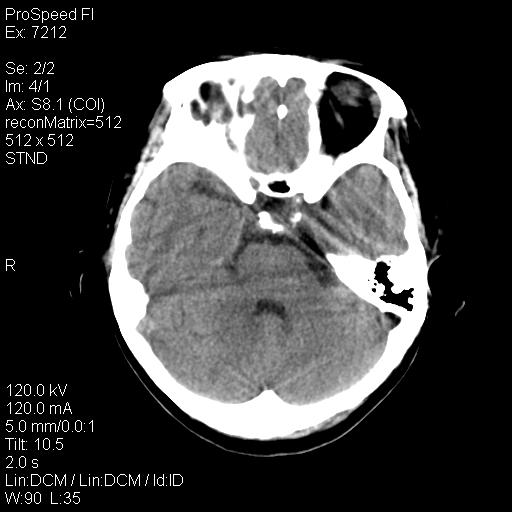

标题: CT18636:F 44Y,头痛三个月,左侧肢体麻木一周。临床诊断, [打印本页]

标题: CT18636:F 44Y,头痛三个月,左侧肢体麻木一周。临床诊断,

右额叶脑沟变浅,脑表面见新月形稍高密度影,考虑慢性硬膜下出血可能。

左侧额颞部慢性英模下血肿。

1)考虑左侧额部慢性硬膜下血肿(或硬膜下积液)。2)颅骨骨髓瘤不排除;建议行进一步检查。

1)考虑左侧额颞部及右侧额部慢性硬膜下血肿(或硬膜下积液)。2)颅骨骨髓瘤不排除;建议行进一步检查。

1)右侧半卵圆中心腔隙性脑梗塞。2)考虑左侧额部慢性硬膜下血肿(或硬膜下积液)。3)颅骨骨髓瘤不排除;建议行进一步检查。